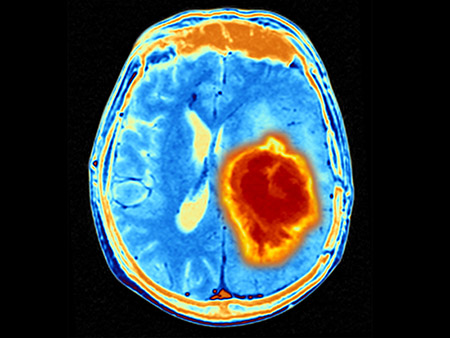

Brain tumour. Coloured Magnetic Resonance Imaging (MRI) scan of an axial section through the brain showing a metastatic tumour. At bottom left is the tumour (red-yellow) This tumour occurs within one cerebral hemisphere; the other hemisphere is at right. The eyeballs - not visible -are at top. Metastatic cancer is a secondary disease spread from cancer elsewhere in the body. Metastatic brain tumours are malignant. Typically they cause brain compression and nerve damageG207, an immunotherapy derived from a modified herpes virus is well tolerated in children with gliomas, and shows signs of clinical effectivenessA modified herpes virus, alone and in combination with radiation, has been shown to be well tolerated with early signs of clinical effectiveness in pediatric patients with high-grade brain tumors, or gliomas, according to findings from researchers at the University of Alabama at Birmingham and Children’s of Alabama. The findings were presented at the virtual American Association for Cancer Research Annual Meeting 2021, held April 10-15 and published online in the New England Journal of Medicine on April 10.